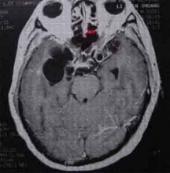

腦寄生蟲病癥狀

• 腦寄生蟲病

628健康網為您分享有關腦寄生蟲病的癥狀,腦寄生蟲病的治療方法,腦寄生蟲病的預防知識,腦寄生蟲病的癥狀圖片,腦寄生蟲病...